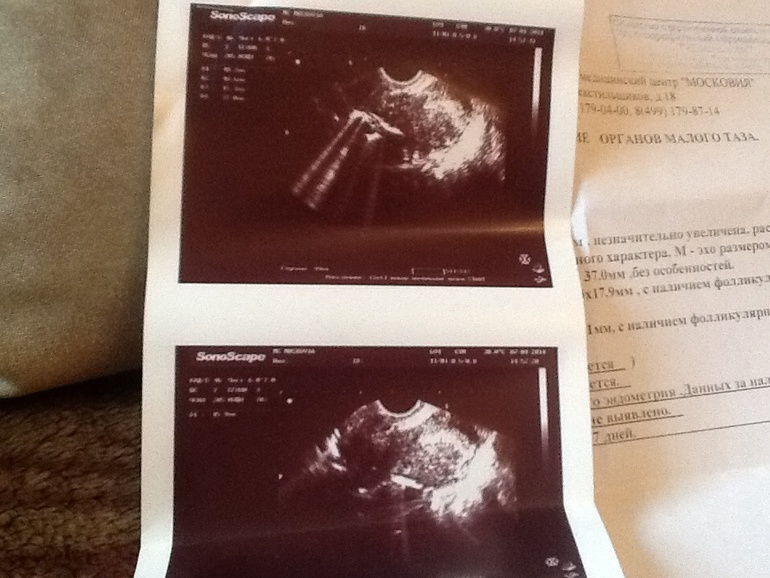

Девочки вообщем ситуация заключается в том,что задержка у меня на сегодняшний день 12-14 дней!записалась я в частную клинику под названием Московия на узи!

Узи делали вагинальное, меньше минуты и врач сказала что не видит моей беременности, сказала приходить повторно через 5-7 дней.

Вот что мне написали в заключении: